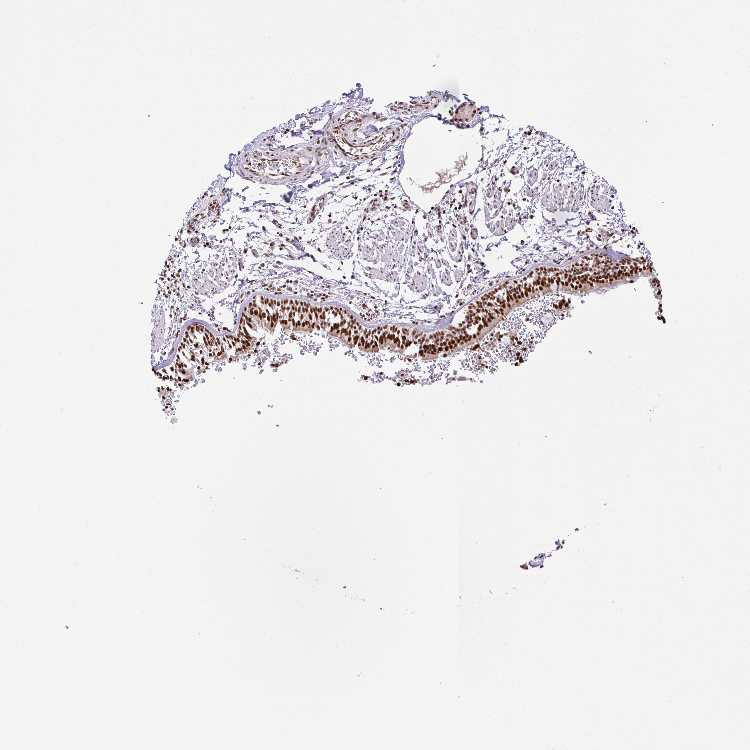

SOFT TISSUE 1 - Antibody stainingi

Antibody staining in the annotated cell types in the current human tissue is reported as not detected, low, medium, or high, based on conventional immunohistochemistry profiling in selected tissues. This score is based on the combination of the staining intensity and fraction of stained cells.

Each image is clickable and will lead to virtual microscopy that enables deeper exploration of all samples and also displays staining intensity scores, fraction scores and subcellular localization as well as patient and tissue information for each sample.

Antibody HPA054823

Chondrocytes Medium

Fibroblasts High

SOFT TISSUE 2 - Antibody stainingi